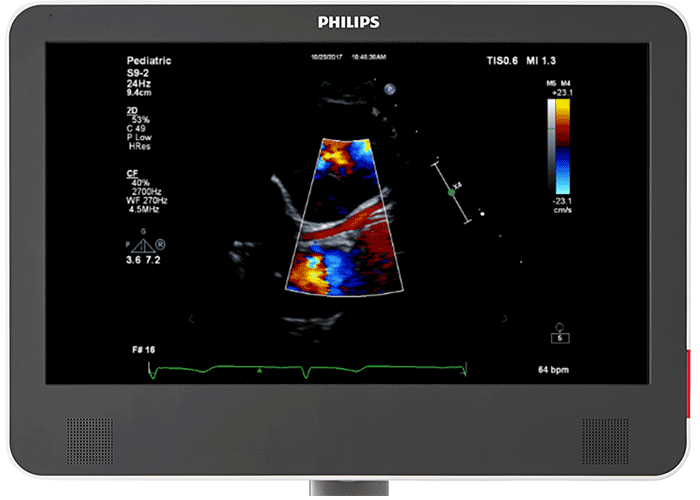

小児心臓用 PureWave トランスジューサ PureWave S9-2 トランスジューサは、シングルクリスタルテクノロジーにより、詳細で優れたコントラスト分解能を有し、さらに超広帯域幅による優れたペネトレーションを実現します。その結果、より深い部位においても詳細な組織情報を低ノイズで取得できます。実際、新型 EPIQ CVx Transcend を見た小児患者担当臨床医の 92%⁶が、新型 PureWave S9-2 トランスジューサはより優れた 2D モードのイメージングを可能にすると回答しました²。

冠動脈の容易かつ迅速な評価 フィリップス EPIQ CVx Transcend のワンボタン式コロナリーサブモード(多くのセクタトランスジューサに搭載)を搭載した新型 EPIQ CVx Transcend を見た小児患者担当臨床医の 92%6が、川崎病、冠動脈異常、冠動脈瘻の病状検出において、現在使用しているシステムよりも EPIQ CVx Transcend のコロナリーサブモードの方が優れていると回答しました2。

鮮明な画像表示 EPIQ CVx Transcend には、22 インチの第二世代有機 EL モニタが搭載されています。180° の視野角を提供し、ダイナミックレンジおよび色範囲も従来製品より拡大しました。さらに、MaxVue による全画面表示により、画像サイズは解像度を犠牲にすることなく従来型超音波画像と比較して 38% 大きくなっています。その結果、並列比較、カラー比較、xPlane、Live 3D、MPRs、負荷エコー画像の機能が強化されました。